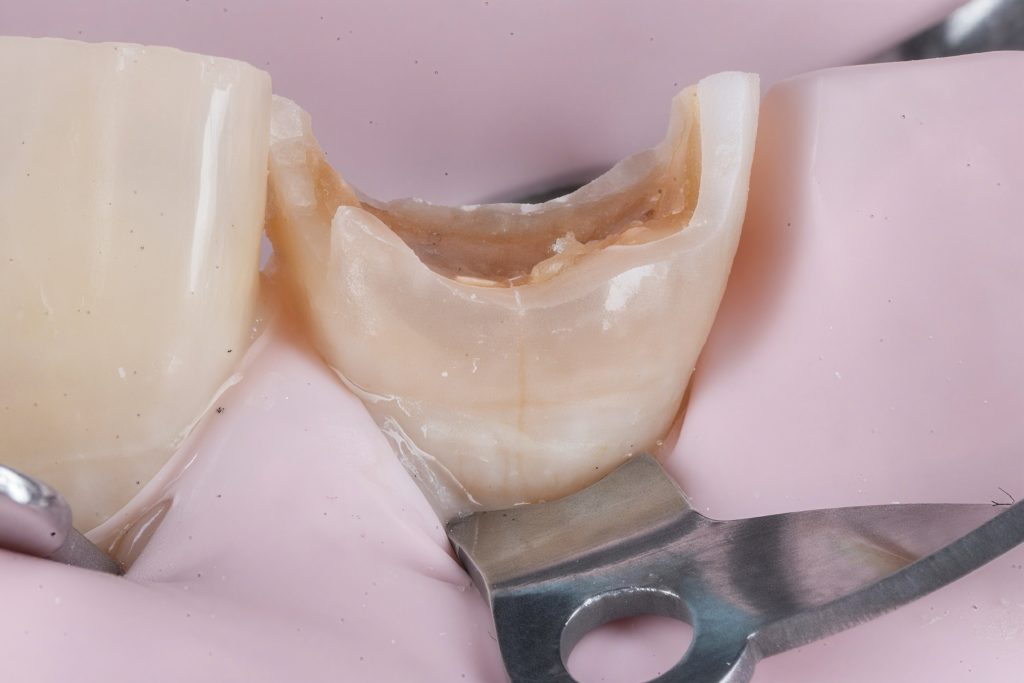

Deep dentin zones were rebuilt using GC EverX Posterior (fiber-reinforced dentin replacement) for internal toughness and crack resistance, followed by Tokuyama Estelite Sigma Quick for enamel layering (Fig 9–10).

Morphology and surface texture were sculpted under microscope vision to achieve natural light diffusion and line-angle harmony.